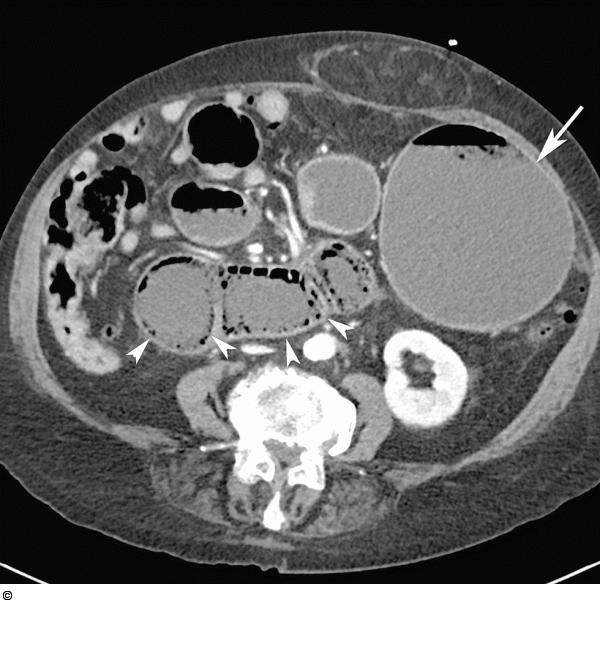

Abbildung 1a: Dilatation Die MDCT in axialer Schicht zeigt eine ausgeprägte Dilatation von Magen (Pfeil) und proximalen Dünndarmschlingen. Diese zeigen auch eine ausgeprägte Pneumatose (Pfeilspitzen). |

Die MDCT in axialer Schicht zeigt eine ausgeprägte Dilatation von Magen (Pfeil) und proximalen Dünndarmschlingen. Diese zeigen auch eine ausgeprägte Pneumatose (Pfeilspitzen). |